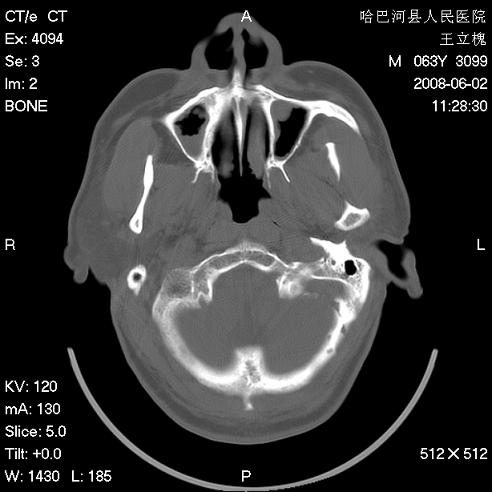

标题: CT13803:反复性鼻塞、流涕一年余 [打印本页]

标题: CT13803:反复性鼻塞、流涕一年余

1.全组副鼻窦炎2.双侧上颌窦积液

.全组副鼻窦炎2.双侧上颌窦积液

1)全副鼻窦炎(左侧上颌窦黏膜下囊肿或息肉)。2)左眼眶肌锥内不规则小结节状软组织密度影;考虑为小血管瘤可能。建议行ct增强扫描检查。

全组副鼻窦炎,左侧肌锥内不规则形软组织肿块影,与眼外肌密度相当,左侧视神经受压,肿块与视神经及眼外肌分界清晰,眼外肌无增粗,眶壁无破坏,球后脂肪间隙不模糊,考虑良性改变,小血管瘤或神经源性肿瘤可能,建议增强扫描。